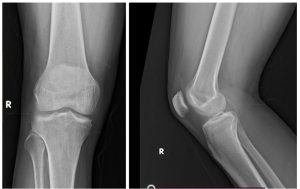

A 25-year-old South Indian man, doing his graduation and playing recreational sports, presented with right knee pain and restricted flexion beyond 100° for the past 4 years and increased in severity for the past 6 months. In 2023, he sought treatment for knee pain and restricted mobility in the form of physiotherapy with no relief from his symptoms Even though the image quality was poor; a cystic lesion could be identified close to the lateral femoral condyle proximal aspect with surrounding soft-tissue edema (Fig. 1). Despite undergoing multiple physiotherapy sessions, the stiffness persisted along with mild intermittent anterolateral knee pain. Although he reported no systemic symptoms, he had pain and discomfort during his regular and sports activities.

During the clinical examination, a point tenderness was appreciated over the lateral femoral condyle with no effusion or synovitis. Range of motion was 0–100° further restricted and associated with pain. The Lachman test indicated no laxity. Collateral ligaments were stable, and no distal neurovascular deficits. MRI images (Fig. 1) reported by the senior musculoskeletal radiologist suggested a probability of nodular synovitis/ganglion cyst/venous malformation as potential diagnoses, as the lesion is <5 cm with no distinct features suggesting toward the SS, it is not included in the differentials. The lesion demonstrated well-defined margins, homogenous signal, lack of aggressive bone or soft-tissue invasion, and no red flags, including periosteal reaction or bone destruction so contrast MRI was not done. Surgery was conducted under general anesthesia and adductor canal block with tourniquet control. Standard anterolateral, anteromedial portals, superolateral, and accessory anterolateral portals were established. During the arthroscopic evaluation, anterior cruciate ligament and posterior cruciate ligament appeared intact and the medial and lateral compartments appeared pristine, except for the lateral gutter showing a cystic swelling adhered to the lateral femoral condyle, we thought of venous malformation/ganglion cyst (Fig. 2 and 3) for which biopsy was obtained and sent for histopathological examination, rest of the lesion removed by using motorized shaver and surrounding tissue was cauterized to ensure lesion free margins and knee portals were closed and regular physiotherapy initiated postoperatively.